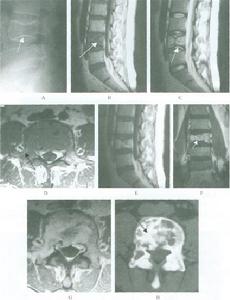

顱底凹陷症合併寰枕融合畸形CT矢狀位重建圖像發病機制

2、CT掃描主要是顯示腦組織及腦室的改變有時可行腦室造影CT掃描在腦室內注入非離子水溶性造影劑後行CT掃描可觀察到腦室大小中腦水管是否通暢及第四腦室及腦幹的改變,並可勾畫出小腦扁桃體下緣的位置

3、MRI檢查MRI是診斷本病最好的檢查手段之一,尤其在矢狀位可清楚的顯示中腦水管第四腦室及腦幹的改變小腦扁桃體下疝的程度及頸髓受壓的情況便於決定手術治療方案